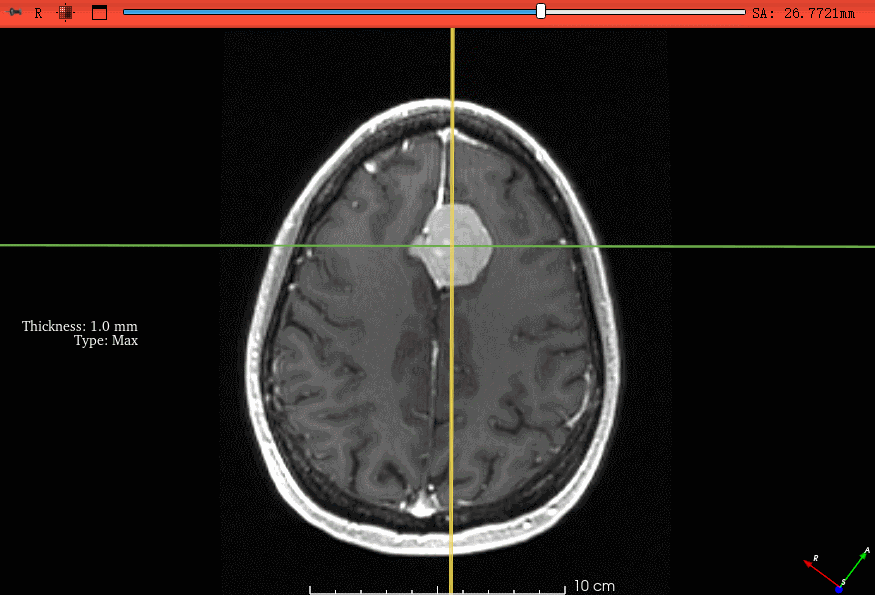

启用后,图像左上角会出现 “Thickness: × mm Type: Max” 提示,表示厚度与投影类型已生效。

GIF 动图展示了在 1 mm 厚度下开启 MIP 后,脑膜瘤强化区的信号更加明亮清晰。